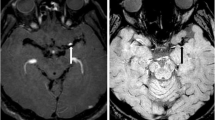

On T1w TSE images all clot types display higher intensity than the MCA and CSF, facilitating clot contrast, especially RBC-rich thrombi; and on T2w DRIVE images, clots with high fibrin content are distinguished by a higher signal. (a–c) Examples of the sequences performed on the test subject using the same MRI scanner and equivalent MRI parameters as in the clot imaging. (a) Axial T1-weighted turbo Inversion Recovery (T1w Turbo IR). (b) Axial T1-weighted turbo spin-echo with fat suppression using Spectral Presaturation with Inversion Recovery (T1w TSE SPIR). (c) Axial T2-weighted turbo spin-echo with DRIVen Equilibrium magnetization refocusing (T2w DRIVE). (d–f) Plots of the four clot groups defined by the fibrin content effect on T1 relaxation times (single-level decision tree, see Fig. 2) by clot signal intensity in each sequence. Reference values: the test subject's white matter (WM), grey matter (GM), cerebrospinal fluid (CSF), and middle cerebral artery (MCA). (d) Boxplot of the T1 clot groups and their intensity signal in T1w turbo IR images. The pairwise comparison showed significant differences in clot intensity in T1w IR between group 4 (fibrin content > 47%) and groups 1 (< 9% fibrin, P < 0.0001), group 2 (9–28% fibrin, P = 0.034), and group 3 (28%–47% fibrin, P = 0.032). (e) Boxplot of the T1 clot groups and their corresponding intensity values in T1w TSE SPIR. There were appreciable signal differences between group 1 and groups 3 (P < 0.001) and 4 (P < 0.0001) and between groups 2 and 4 (P = 0.026). (f) Boxplot of clot groups on T1 times by observed T2w DRIVE signal intensity. Clot analogs in group 4 showed significantly different intensities than the other groups [group 1 (P < 0.0001); group 2 (P = 0.003); group 3 (P = 0.006)].

Regardless of their histology all clots are distinguishable from a patent artery in T1w TSE images

To translate our results into actual practice, we exploratively compared normalized clot intensities with the normalized brain signal intensities of grey matter (GM), white matter (WM), cerebrospinal fluid (CSF), and the middle cerebral artery (MCA) of a test subject. Figure 4 summarizes these results.

In T1w IR (Fig. 4a and d), the average intensity of a patent MCA was in-between the signals for WM and GM, distinguishable from the CSF, which exhibited the lowest intensities. Nevertheless, the vast majority of clots showed intensities below the MCA, falling in an intensity range similar to that of GM and thus limiting the ability to identify clots in a real setting with the IR sequence used here.

On the other hand, in T1w TSE images (Fig. 4b and e) the signal of a patent MCA is low, darker than the surrounding CSF and considerably below GM and WM signal intensities. Here, all clot groups, regardless of their histology, entail a notable increase in the signal intensity of the MCA, but they not overcome the high signal intensity of brain parenchyma (Fig. 4b). Although the higher the intensity of thrombi on T1w TSE sequences, the lower the fibrin content, the possibility of discriminating among all clot histologies might be limited because of the narrow intensity range in which all four groups are located (Fig. 4e).

T2w DRIVE images readily detect thrombi of > 47% fibrin content, the more fibrin, the greater clot hyperintensity

In the T2w DRIVE sequence, arteries and brain parenchyma have very low signal intensities, in contrast to CSF, which is hyperintense (Fig. 4c and f). Only a few thrombi with very high iron content may not be distinguishable from the neighboring GM or MCA in T2w DRIVE sequences, though most should exhibit higher signals than the MCA proper. Notably, the highest signal intensities were recorded for thrombi with more than 47% fibrin which, in some cases, could even reach the signal intensity of the CSF (group 4, Fig. 4f).